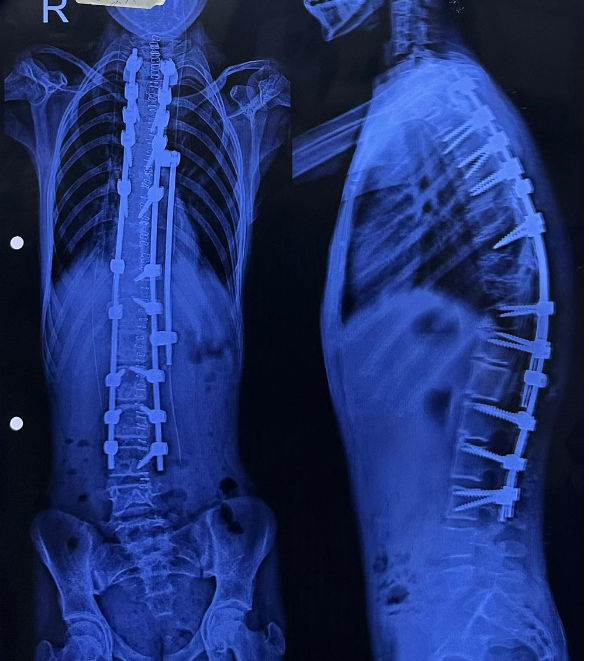

Ahmedabad News: અમદાવાદ સિવિલ મેડિસિટી સ્થિત ગવર્નમેન્ટ સ્પાઈન ઈન્સ્ટિટ્યૂટ ફરી એકવાર માનવીય સેવા મહેકાવી છે. આરોગ્ય વિભાગના સહયોગથી આયોજિત ‘ઈન્ડો-અમેરિકન સ્પાઇન સર્જરી કેમ્પ’ અંતર્ગત કરોડરજ્જુની અત્યંત જટિલ વિકૃતિ ધરાવતા 7 બાળકોનું સફળ ઓપરેશન કરવામાં આવ્યું છે. વૈશ્વિક આંકડા મુજબ દર 1000 બાળકોમાં 1 બાળકમાં જોવા મળતી કાઇફોસિસ અને સ્કોલિયોસિસ જેવી વિકૃતિઓ સામે આ કેમ્પ એક નવી આશા લઈને આવ્યો છે.

‘કાઇફોસ્કોલિયોસિસ’ એક ગંભીર બીમારી છે, જેમાં બાળકની કરોડરજ્જુ સાપની જેમ વાંકી વળી જાય છે, તેની સારવાર સામાન્ય મધ્યમ વર્ગ માટે એક સ્વપ્ન સમાન હોય છે. પરંતુ, ઈન્ડો-અમેરિકન સર્જરી કેમ્પના માધ્યમથી આ સ્વપ્ન હકીકત બન્યું છે. સર્જરીની જટિલતા અંગે ઈન્ડો-અમેરિકન સર્જરી કેમ્પના ડૉક્ટરો જણાવે છે કે, આ એક અત્યંત જટિલ સર્જરી છે. સરેરાશ 4 થી 5 કલાક સુધી ચાલતી આ સર્જરીમાં કરોડરજ્જુને સીધી કરતી વખતે અત્યંત નાજુક ચેતાઓ (Nerves) અને રક્તવાહિનીઓ વચ્ચે કામ કરવાનું હોય છે.

સર્જરી દરમિયાન મુખ્ય પડકાર સતત ‘ન્યુરો-મોનિટરિંગ’નો હોય છે. જો કોઈ પણ પગલું ખોટું પડે, તો મુખ્ય રક્તવાહિનીની ઈજાને કારણે દર્દીનો જીવ જઈ શકે છે અથવા જીવનભરનો લકવો (Paralysis) આવી શકે છે. આ જોખમને ખાળવા માટે અમેરિકન ન્યુરો-મોનિટરિંગ ટીમ અને એનેસ્થેસિયા નિષ્ણાતોએ પણ ટેકનિકલ સહયોગ આપ્યો હતો.

આ પ્રકારની જટિલ સર્જરીનો ખર્ચ ખાનગી હોસ્પિટલોમાં રૂ. 5 થી 10 લાખ જેટલો આંકવામાં આવે છે. ગવર્નમેન્ટ સ્પાઈન ઈન્સ્ટિટ્યૂટ વર્ષ દરમિયાન આવી 30 થી 40 સર્જરીઓ કરે છે. આ કેમ્પમાં 9 વર્ષના એક બાળક પર ‘ગ્રોઇંગ રોડ સર્જરી’ કરવામાં આવી હતી, જે આધુનિક મેડિકલ સાયન્સનું શ્રેષ્ઠ ઉદાહરણ છે. આ ‘ગ્રોઇંગ રોડ સર્જરી’ બાળકની ઉંમર વધવાની સાથે તેની કરોડરજ્જુને સીધી રાખવામાં મદદ કરશે. આ કેમ્પના આયોજનથી માત્ર ગુજરાત જ નહીં પરંતુ દેશના અન્ય રાજ્યોમાંથી આવેલા બાળકો અને દર્દીઓનેને લાભ આપવામાં આવ્યો છે. આરોગ્ય રાજ્યમંત્રીએ ઈન્ડો-અમેરિકન ડૉક્ટરોના માનવીય અભિગમને બિરદાવ્યો હતો.